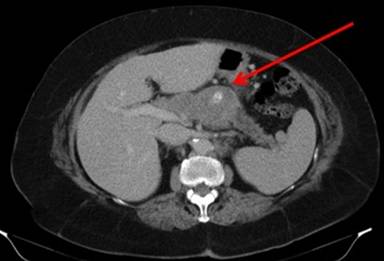

A 62-year-old Caucasian woman from regional Australia presented to our hospital in 2013 for investigation of a pancreatic mass found on CT whilst being investigated by her general practitioner for epigastric pain, bloating and anorexia. The scan showed a large mid-body pancreatic mass with vascular involvement, thought to be most likely a primary pancreatic tumour, and she was referred to our unit for further treatment (Figure 1). Her tumour markers including CA 19.9 were normal and after discussion in the multi-disciplinary meeting she underwent a trans-hepatic percutaneous biopsy for this unresectable mass. Pathological examination of this tissue showed CD56 and CK20 positivity and two independent pathologists reported it to be most likely of Merkel cell carcinoma origin.

Figure1. Large mid-pancreatic body mass. |